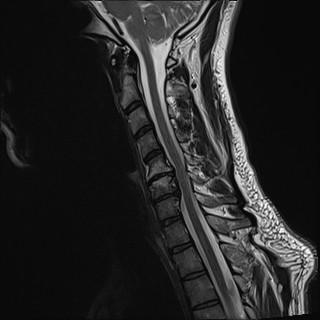

Wirbelsäule HWS

t2_tse_sag